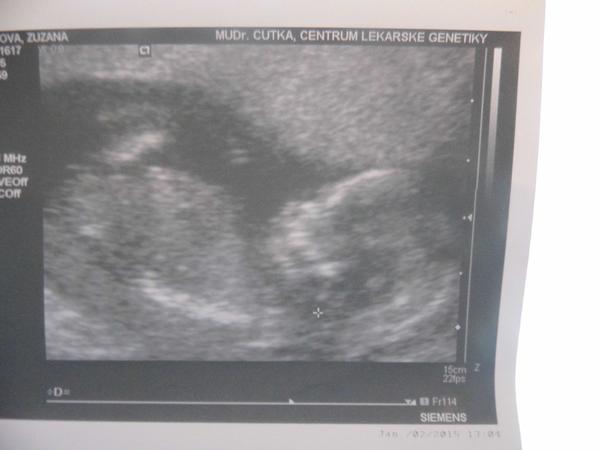

@muddledgirl Ahoj holky, tak takhle rosteme, toto je dnešní UTZ, tj 14tt. A na 90% to bude princezna 😀 Všechno je v pořádku a jsme zdraví!